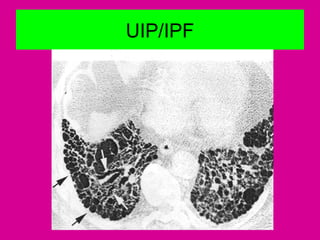

UIP/IPF

Reticular opacities, traction

bronchiectasis + HC

• Honeycombing with a basal and subpleural redominance

is highly suggestive of UIP.Lung biopsy is rarely

performed when HRCT shows these findings.